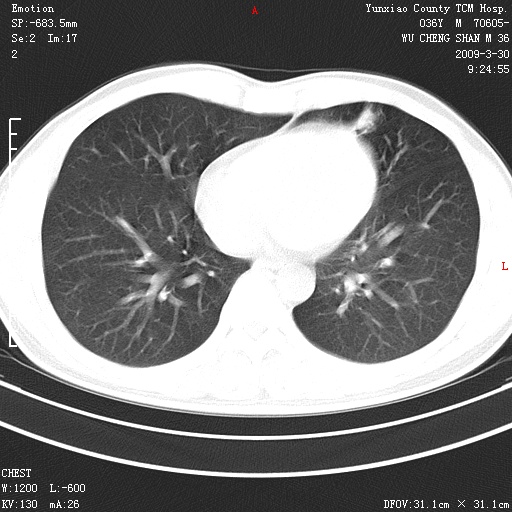

本院家属,胸痛,无咳嗽咳痰发烧病史,治疗一个月后病灶无明显改变,支气管镜示左肺慢性炎症,未见癌细胞,

胸痛,无咳嗽咳痰发烧病史,治疗一个月后病灶无明显改变,支气管镜示左肺慢性炎症,未见癌细胞,左肺下叶前段片状影,边缘不清,内见空支气管征,纵隔未见淋巴结肿大,周围无卫星灶,应考虑为炎性病变。

胸痛,无咳嗽咳痰发烧病史,治疗一个月后病灶无明显改变,支气管镜示左肺慢性炎症,未见癌细胞,左肺舌叶片状影,边缘不清,内见空支气管征,周围无卫星灶,应考虑为炎性病变。

病灶分散,考虑炎性

左肺舌叶片状影,边缘不清,内见空支气管征,炎性病变